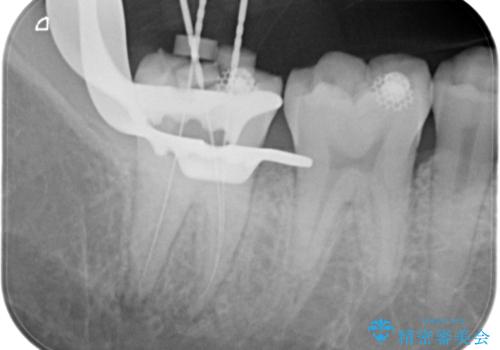

【根管治療】ズキズキ痛い歯の治療

- 奥歯がズキズキ痛いことを主訴に来院されました。

不可逆性歯髄炎の診断により根管治療を行なっております。

根管治療を行なった歯は速やかに歯冠修復が必要です。